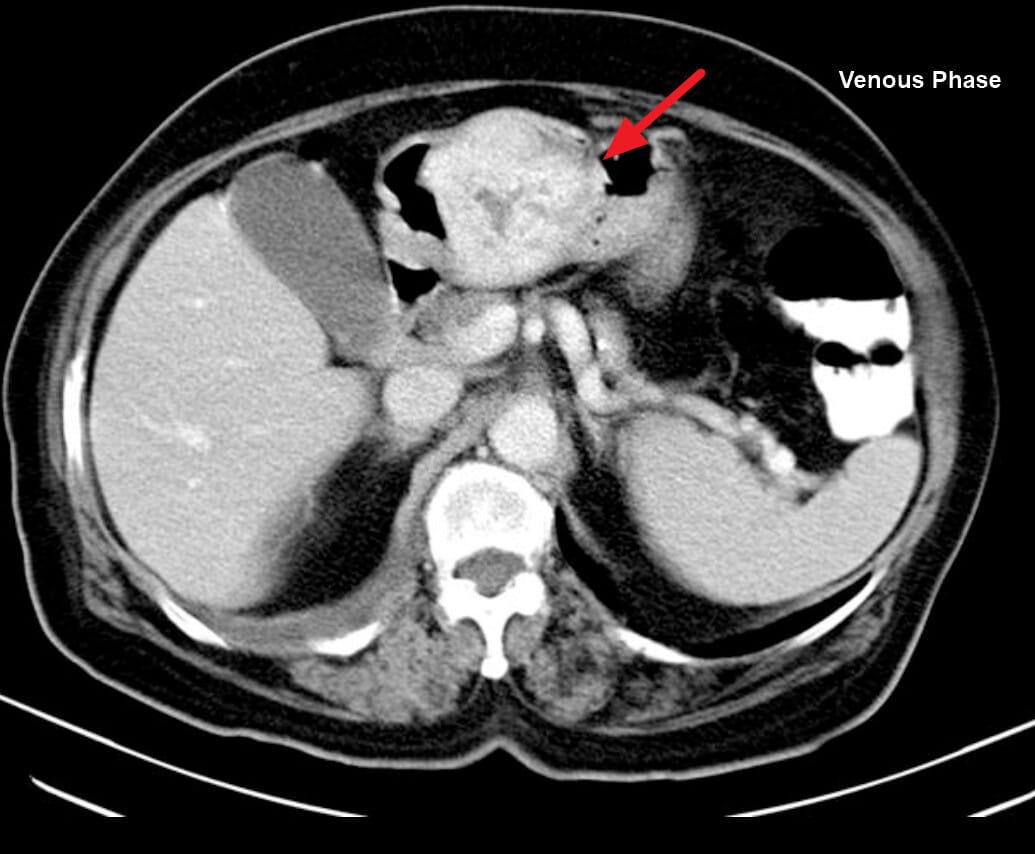

🔵 복부 CT

위벽 비후, 림프절 종대, 인접 장기 침윤, 간 등으로의 전이 확인

Stomach Cancer – 영상 소견상 특징

• Wall thickening and irregular enhancing mass in the gastric antrum region. (Portal venous phase / Delayed Phase)

Niknejad M, Gastric carcinoid tumor. Case study, Radiopaedia.org (Accessed on 14 Jul 2025) https://doi.org/10.53347/rID-201554

Gaillard F, Gastric adenocarcinoma. Case study, Radiopaedia.org (Accessed on 14 Jul 2025) https://doi.org/10.53347/rID-15047

Cuete D, Gastric carcinoma.

Case study, Radiopaedia.org (Accessed on 14 Jul 2025) https://doi.org/10.53347/rID-30234